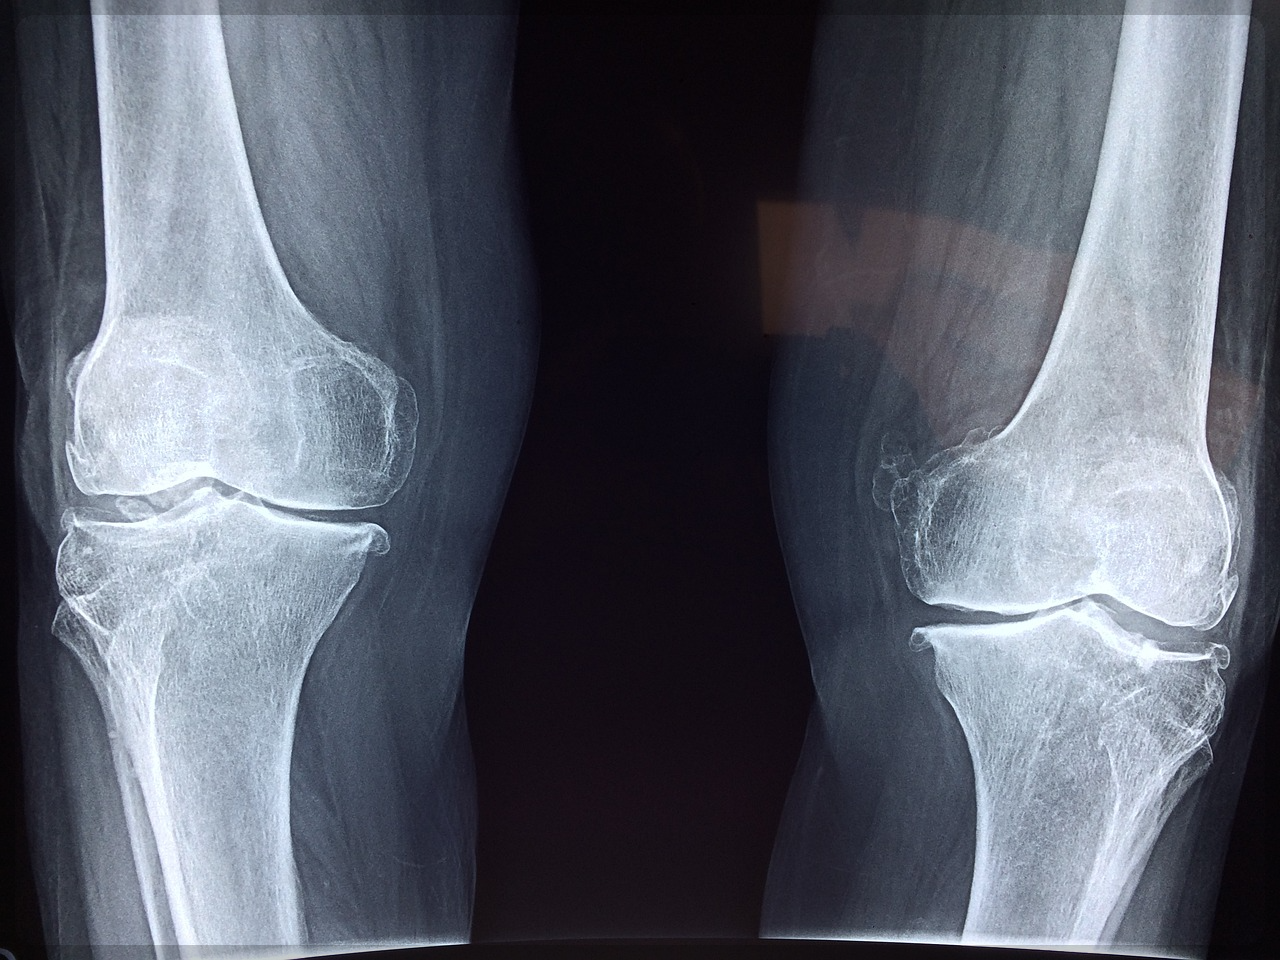

40대 이상 성인 90%가 관절 퇴행성 변화를 겪고 있고 50대 3명 중 1명 그리고 65세 이상 2명 중 1명은

이미 관절염을 앓고 있다고 합니다.

게다가 65세 이상 연령대에서는 무릎 관절염 발생률이 58.2%, 골관절염 발생률은 68.1%로 아주 높게 나타나는데요.

그러다 보니 75세 이상이 되면 대부분 관절염을 앓게 된다고 합니다.

즉 관절 건강 수명은 평균 60세밖에 되지 않는다는 뜻인데요.

우리나라 평균 기대수명이 83.5세라는 걸 감안하면 관절로 인해 움직일 때마다 고통받는 기간은 무려 20년이

넘는다는 겁니다.